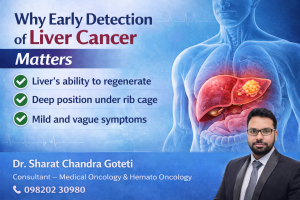

Why early detection of liver cancer is important.

As noted by Dr. Sharat Chandra Goteti, liver cancer is frequently identified late for numerous reasons:

- The liver’s capacity to repair and recover from injury

- Its deep position within the rib cage

- Symptoms that are minor and easily confused

As a result, Dr. Sharat Chandra Goteti emphasizes the importance of regular health screenings, particularly for those at high risk. Dr. Sharat Chandra Goteti’s early diagnosis can boost treatment outcomes greatly.